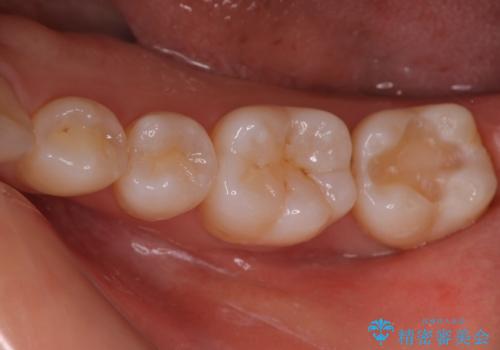

銀歯を白いセラミックに変えたい セラミックインレー

- 銀歯が気になるためやり替えたいとのことで来院されました。

セラミックインレーで治療を行いました。

口の中にチラつく銀歯は適合の良いセラミックインレーでやり替えることで綺麗にやり替えることができます。